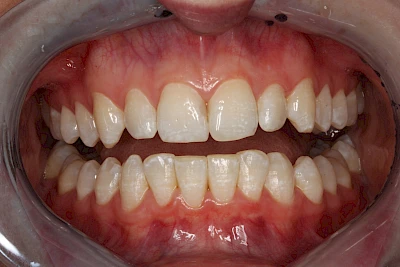

Verfärbungen an Zähnen können außen aufgelagert oder im Zahn eingelagert sein.

Daneben gibt es noch seltene genetisch bedingte Schmelz- bzw. Dentinbildungsstörungen (Amelogenesis imperfecta, Dentinogenesis imperfecta), die neben Verfärbungen vor allem auch durch Veränderungen der Oberflächenstrukturen auffallen. In diesen Fällen ist eine engmaschige Betreuung durch den Zahnarzt wichtig.